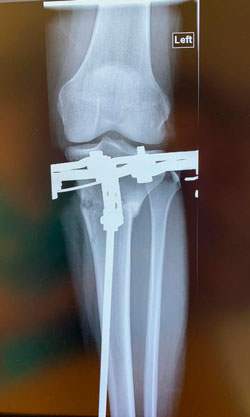

Рентген перед снятием аппаратов 85 дней

Дата операции - 11.10.2019.

Дата снятия аппаратов 14.01.2020

Срок сращения 93 дня.